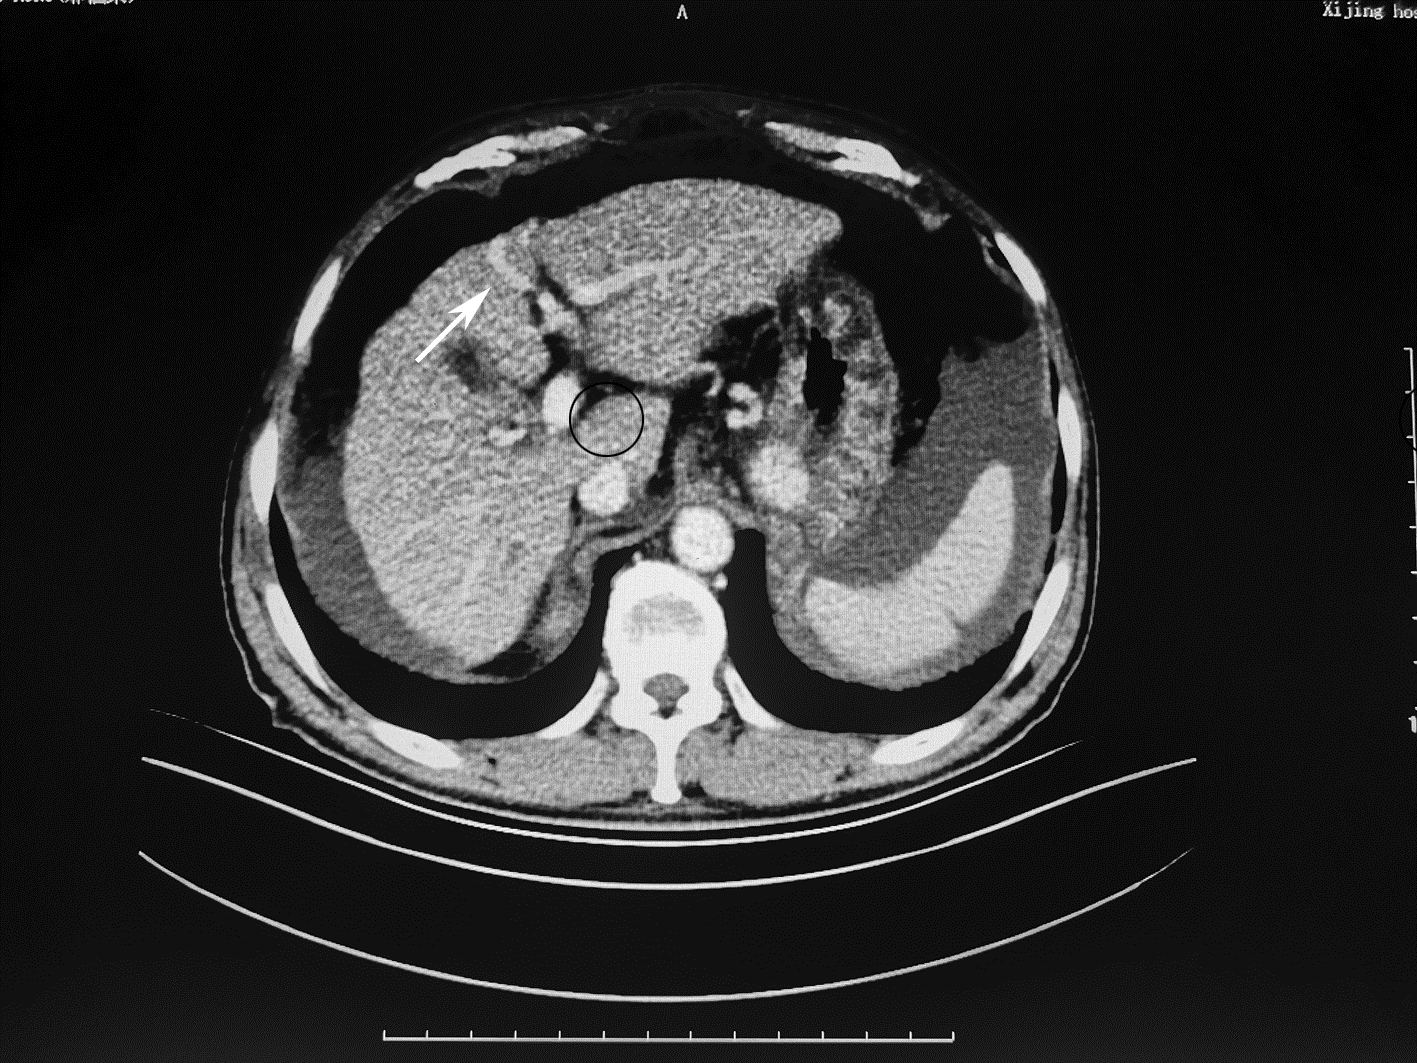

Local embolization combined with targeted comprehensive immunotherapy in treatment of sarcomatoid hepatocellular carcinoma: A case report

Jin LEI, Linzhi ZHANG, Yinying LU, Bowen CHEN, Shi ZUO

2022, 38(4): 880-882. DOI: 10.3969/j.issn.1001-5256.2022.04.026

Abstract(1335) HTML (456) PDF (3487KB)(84)

Abstract: